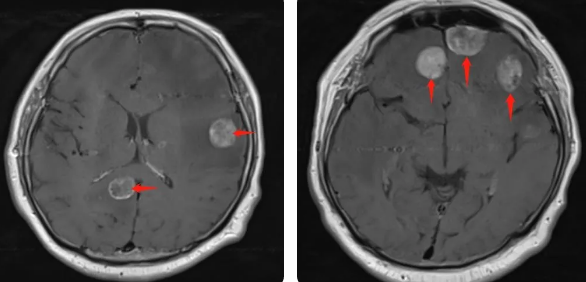

無獨有偶,60歲的左肺癌患者石先生,在外院接受了手術(shù)治療,結(jié)果術(shù)后10月出現(xiàn)腫瘤腦轉(zhuǎn)移,頭部增強MRI顯示:顱內(nèi)多發(fā)占位性病變伴水腫,接二連三的重擊讓石先生出現(xiàn)表情淡漠,沉默寡言,絕食等抑郁癥狀,VMAT放療技術(shù)與心理疏導(dǎo)雙管齊下,3周的治療后顱內(nèi)轉(zhuǎn)移病灶顯著縮小,部分甚至消失,困擾石先生的頭痛、頭暈癥狀也不復(fù)存在,石先生重拾對生活的希望,也對未來的治療充滿信心。